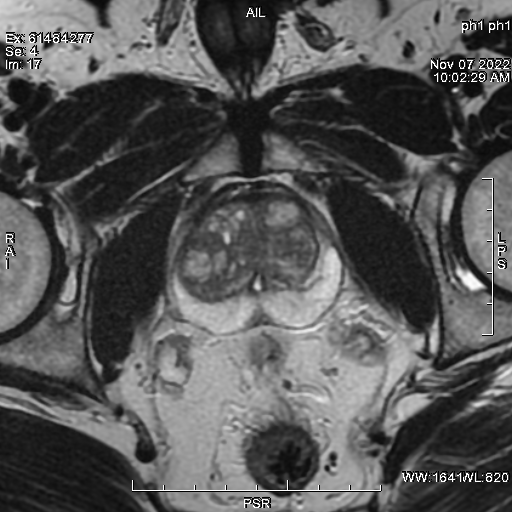

IRM de la prostate

Lors d’un EPU sur le cancer de la prostate (enseignement post universitaire) dans le cadre du mois de novembre bleu

organisé par la société d’oncologie médicale de l’ouest et l’établissement hospitalo-universitaire 1er novembre (EHU) sous le sponsor de STRATMEDINNOVE ; Dr H.Derriche a animé un atelier sur IRM de la prostate.